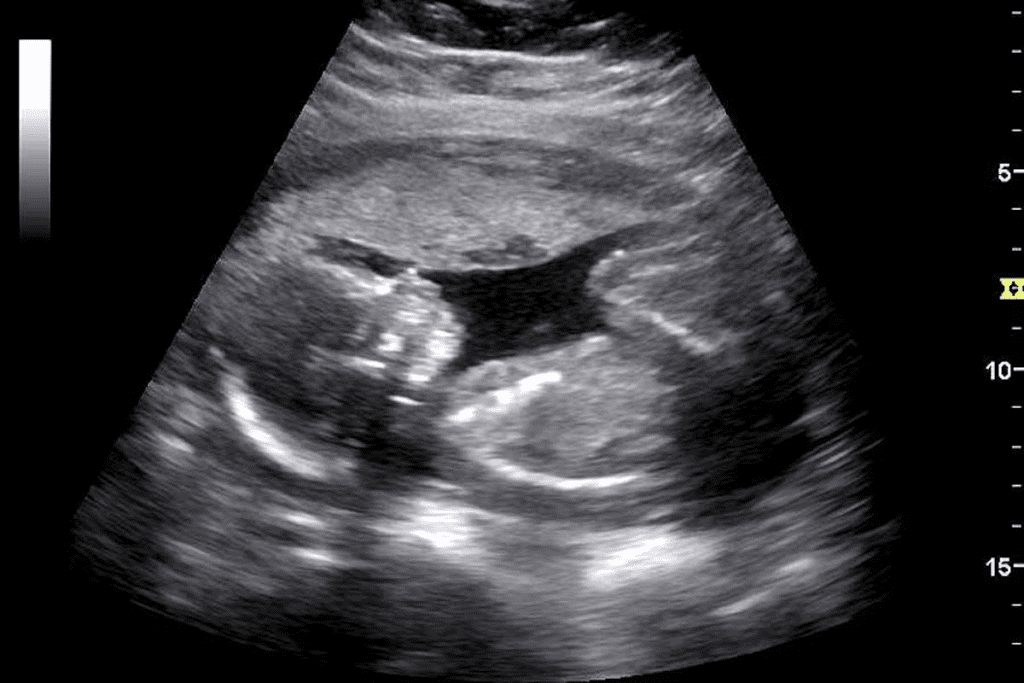

Did you know millions of ultrasounds are done every year in the U.S.? Many of these show black masses, which can worry people. Interpret what a black mass signifies on an ultrasound picture and when it indicates a concern versus a normal finding.

Knowing what a black mass on an ultrasound image means is key for both patients and doctors. Ultrasound tech is a big help in checking our insides. A black mass might mean anything from harmless cysts to serious problems.

It’s important to understand what black areas on ultrasound images mean. They can show different things, from harmless fluid-filled areas to serious masses.

Anechoic Structures: Fluid-Filled vs. Solid Masses

Anechoic structures look black because they don’t bounce sound waves back. They are usually filled with fluid, like cysts or gallbladders. Anechoic structures have no internal echoes, unlike solid masses that do.

Fluid-filled anechoic structures are often harmless, like simple cysts in the kidney or liver. But, some black areas might be solid masses that look uniform but are rare.

Black masses on ultrasound pictures can mean many things, from simple cysts to complex blood vessels. Knowing what they are helps doctors make the right diagnosis and care plan.